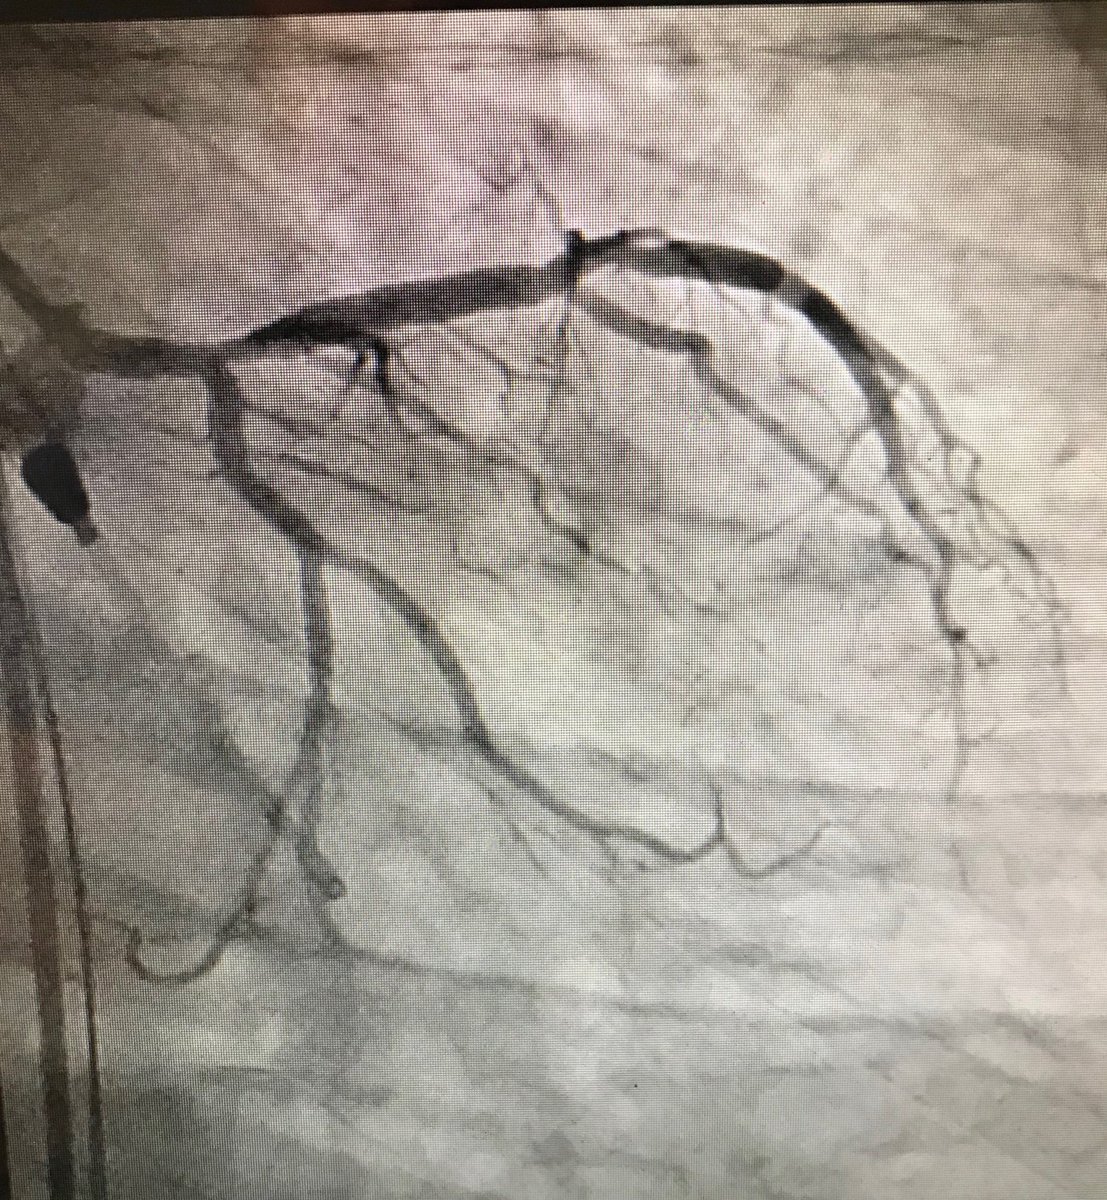

45f #cardiotwitter #safefemoral ,2 hrs symptoms,3am case, #stemi stent into left main from LAD.no#shock ,no#impella. EF40.#alifesaved

istentem's tweet image. 45f #cardiotwitter #safefemoral ,2 hrs symptoms,3am case, #stemi stent into left main from LAD.no#shock ,no#impella. EF40.#alifesaved